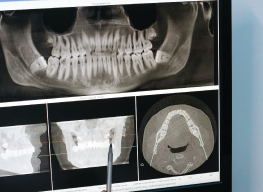

Initial Consultation and Planning: This includes a comprehensive dental examination, X-rays, and sometimes 3D imaging. The dentist evaluates the condition of your jawbone and develops a personalized treatment plan.